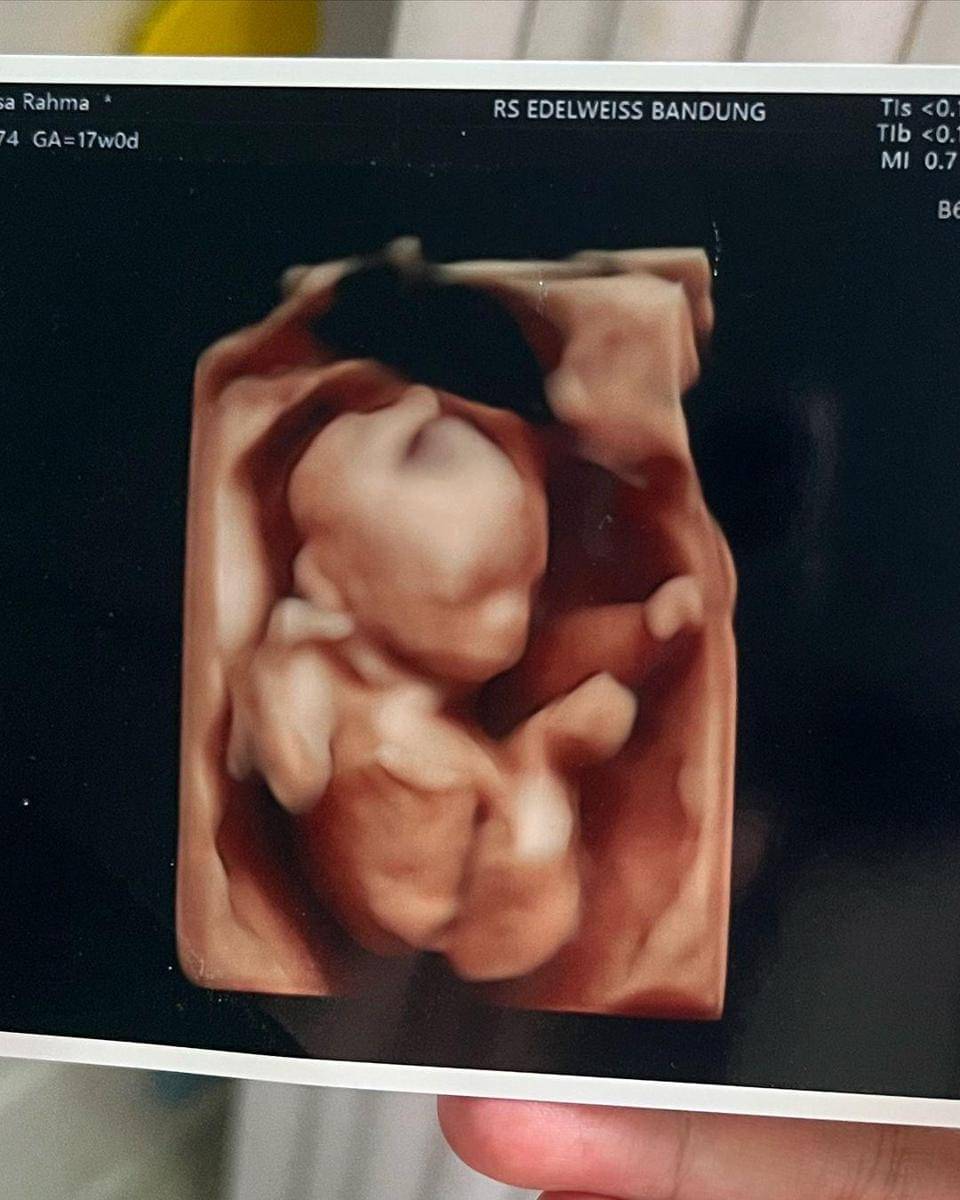

Selain mengunggah foto dirinya memegang test pack, Anisa juga memperlihatkan foto hasil USG janin yang ada di dalam kandungannya. Seperti yang terlihat, Anisa memeriksakan kandungannya di RS Edelweiss Bandung.

Tak hanya itu, terlihat pula keterangan GA (gestational age) yang menunjukan perkiraan umur kehamilan. Dari tulisan yang terlihat, terungkap kehamilan Anisa telah berusia 17 minggu atau sekitar 4 bulan.